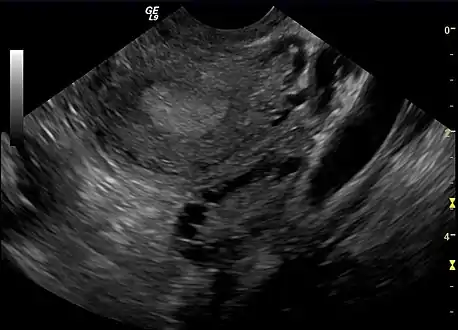

A polycystic ovary

The syndrome acquired its most widely used name due to the common sign on ultrasound examination of multiple (poly) ovarian cysts. These "cysts" are in fact immature ovarian follicles. The follicles have developed from primordial follicles, but this development has stopped ("arrested") at an early stage, due to the disturbed ovarian function. The follicles may be oriented along the ovarian periphery, appearing as a 'string of pearls' on ultrasound examination.[86]

• Gynecologic ultrasonography, specifically looking for small ovarian follicles. These are believed to be the result of disturbed ovarian function with failed ovulation, reflected by the infrequent or absent menstruation that is typical of the condition. In a normal menstrual cycle, one egg is released from a dominant follicle – in essence, a cyst that bursts to release the egg. After ovulation, the follicle remnant is transformed into a progesterone-producing corpus luteum, which shrinks and disappears after approximately 12–14 days. In PCOS, there is a so-called "follicular arrest"; i.e., several follicles develop to a size of 5–7 mm, but not further. No single follicle reaches the preovulatory size (16 mm or more). According to the Rotterdam criteria, which are widely used for diagnosis of PCOS,[10] 12 or more small follicles should be seen in a suspect ovary on ultrasound examination.[21] More recent research suggests that there should be at least 25 follicles in an ovary to designate it as having polycystic ovarian morphology (PCOM) in women aged 18–35 years.[95] The follicles may be oriented in the periphery, giving the appearance of a 'string of pearls'.[96] If a high-resolution transvaginal ultrasonography machine is not available, an ovarian volume of at least 10 ml is regarded as an acceptable definition of having polycystic ovarian morphology. rather than follicle count.[95]

Most common names for this disease derive from a typical finding on medical images, called a polycystic ovary. A polycystic ovary has an abnormally large number of developing eggs visible near its surface, looking like many small cysts.[91]